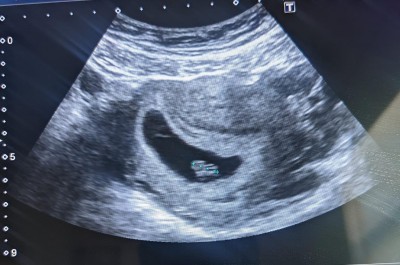

image

kız bebek benim ki böyle idi

Benimkine benziyor kuzeniminki farklı duruyor

Sağol canım:))